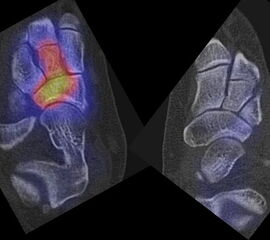

Die Abbildungen 4.2.a bis d zeigen den typischen Aspekt einer talacalcanearen Coalitio. Es besteht nur eine linksseitige, symptomatische Coalitio talocalcaneare (4.2.a und c); das 35 Tage zuvor angefertigte MRT zeigt keine auffälligen Signalveränderungen (4.2.b und d).

Abbildung 4.3. zeigt die Ursache für rechtsseitige Sprunggelenksbeschwerden bei einem Patienten mit talocalcanearen Coalitionen: nur die osteochondrale Läsion an der distalen rechten Tibia ist die Ursache des Schmerzes. Die bilateralen talocalcanearen Coalitionen sind asymptomatisch.